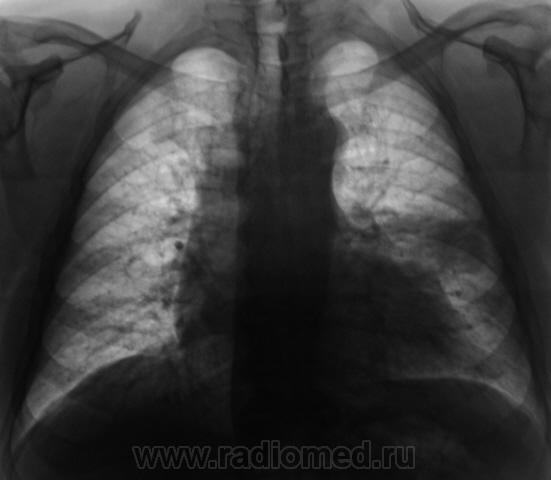

Начало 2008 года. При расшифровке флюорограмм, пациента "взяли на контроль", заподозрили периферический рак левого лёгкого (по "прямой" флюорограмме). Вроде-бы все правильно и логично?

Но мы, пациента дообследовали, рентгенография и томография (аналоговая), высказали мнение о наличии "опухолевого роста" и рекомендовали консультацию онколога, и пациент "поехал" туда, куда послали. Снимков (тех первых) предоставить не могу, остались там, куда "послали". Выписка "рекомендовала" понаблюдать....

В апреле 2009 года пациент пришел "для динамического наблюдения" - серия 2.

После повторного дообследования (апрель 2009 г) - 2 серия изображений, мы были твердо уверены, что пациент взят на учет..., но не тут-то было. В пятницу рентгенолаборант флюорографа попросил подойти и "глянуть снимок"...

Оказывается "данный" пациент направлен для прохождения профилактической флюорографии..., так как надо было поменять водительские права...?

Вот флюорограммы.